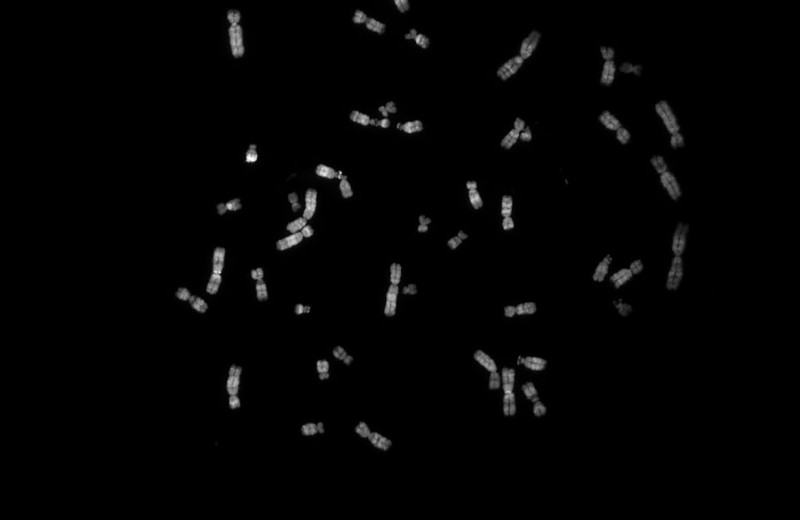

Из чего же сделаны наши мальчишки и девчонки Из чего же сделаны наши мальчишки и девчонки

Что именно мы наследуем от мамы, а что — от папы?